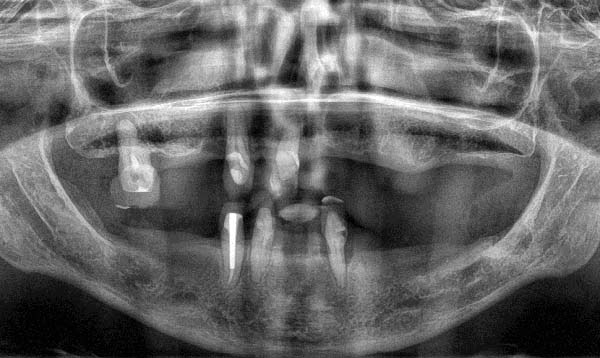

Je drei verbliebene Zähne im Ober- und Unterkiefer, weit aufgefächert, mit Lockerungen dritten Grades und sekundär gewandert, über 70 Prozent Knochenabbau.